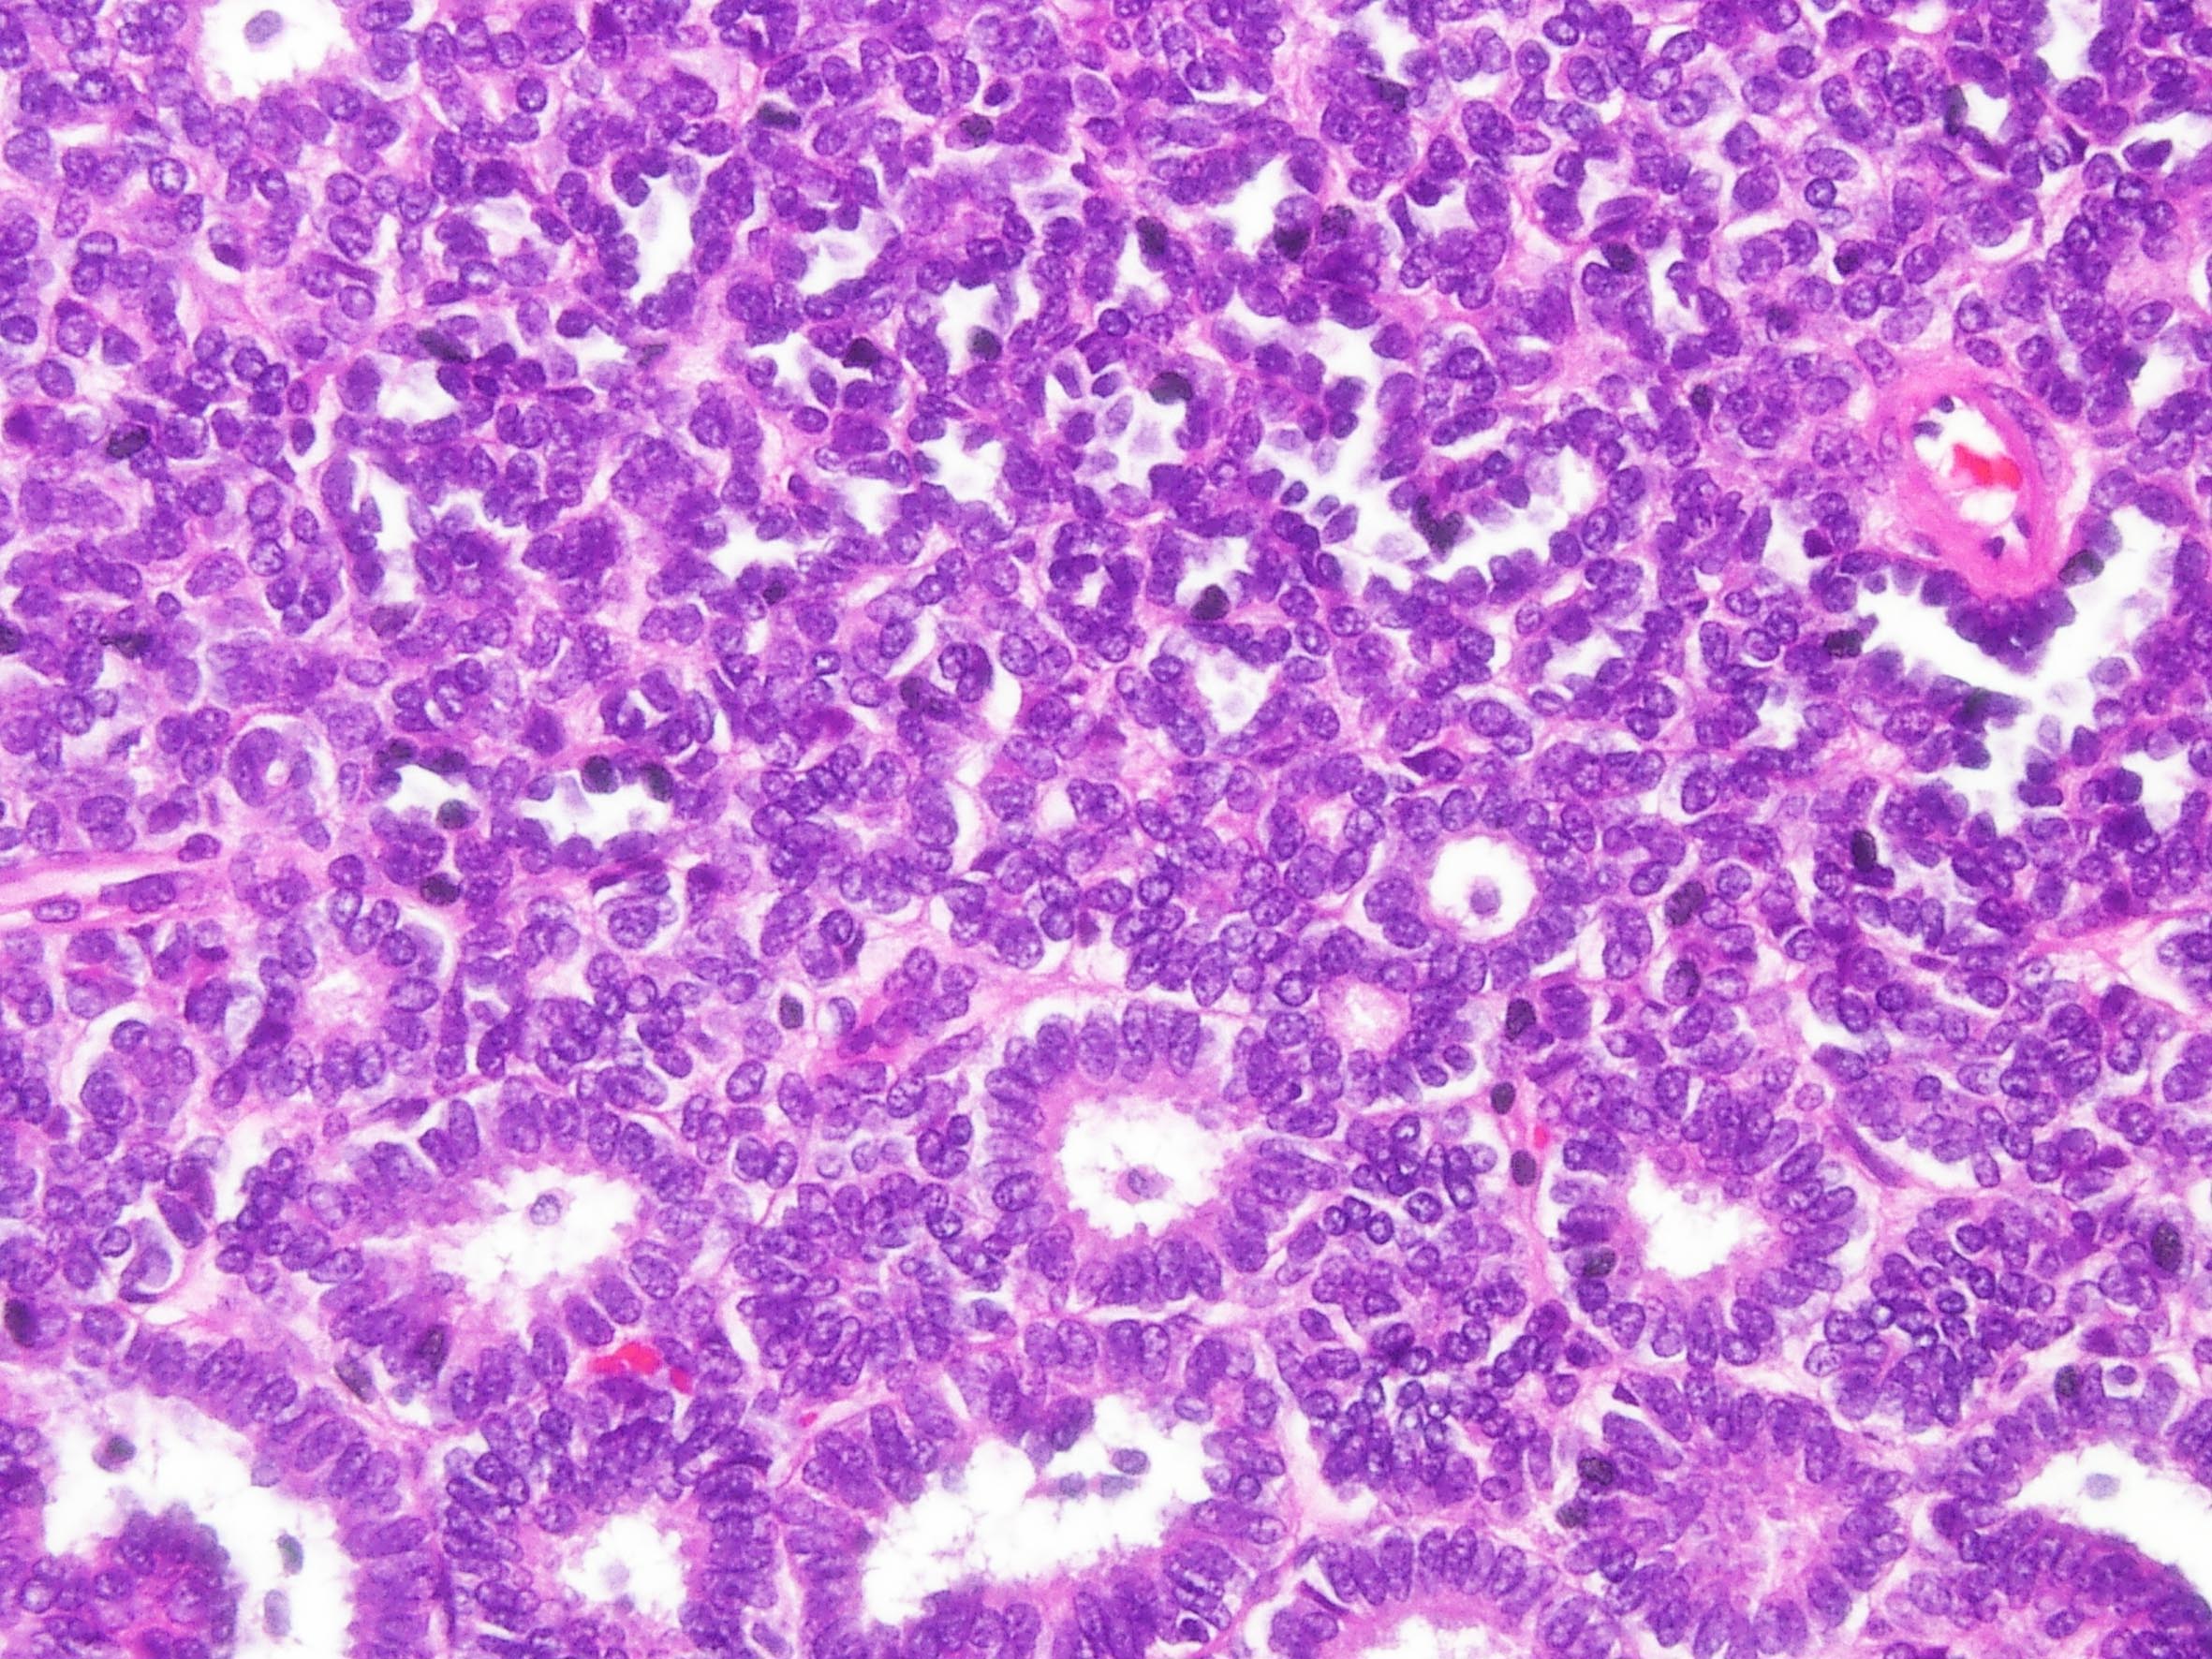

Metanephric adenoma